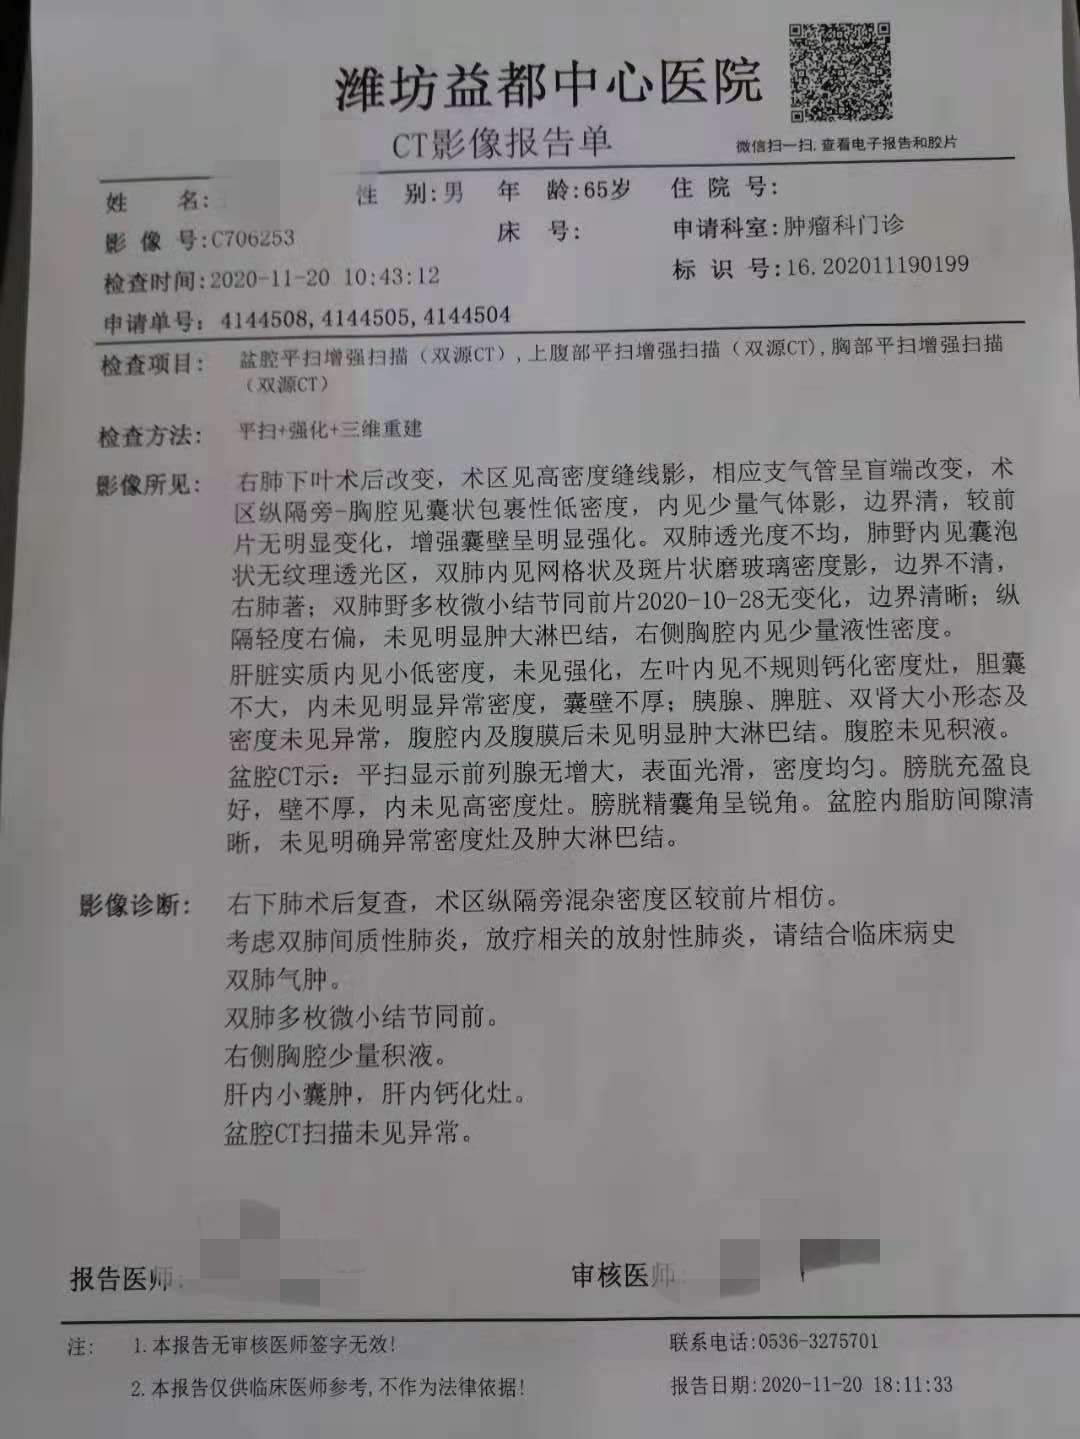

刚才去打印出ct片子加报告单,显示间质性肺炎。二十天前的ct片子显示放射性肺炎明显好转,感觉就快完全好了,一个感冒又两肺爆发肺炎。

这次肿瘤标志物三项超出正常值,因为偶尔会头晕恶心,预约了明天的核磁共振。下图分别是这次的ct报告单,前后两次ct片子对比,这次肿瘤标志物。